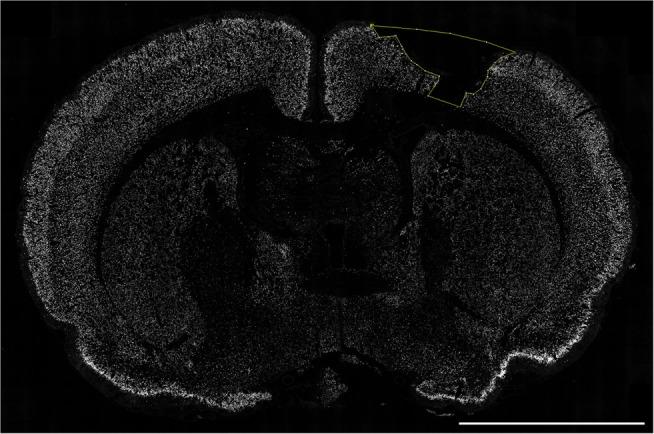

Female Sprague-Dawley rats (n = 73, including sham and naive) were used. The rats were intubated and mechanically ventilated. A controlled cortical impact device created a 3-mm deep lesion in the right parietal hemisphere. Post-injury, rats inhaled either normoxic (22% O2) or hypoxic (11% O2) mixtures for 30 min. The rats were sacrificed at 1, 3, 7, 14, and 28 days post-injury. Serum was collected for S100B measurements using ELISA. Ex vivo magnetic resonance imaging (MRI) was performed to determine lesion size and edema volume. Immunofluorescence was employed to analyze neuronal death, changes in cerebral macrophage- and neutrophil infiltration, microglia proliferation, apoptosis, complement activation (C5b9), IgG extravasation, HIF-1α, and VEGF.

The hypoxic group had significantly increased blood levels of lactate and decreased pO2 (p < 0.0001). On MRI post-traumatic hypoxia resulted in larger lesion areas (p = 0.0173), and NeuN staining revealed greater neuronal loss (p = 0.0253). HIF-1α and VEGF expression was significantly increased in normoxic but not in hypoxic animals (p < 0.05). A trend was seen for serum levels of S100B to be higher in the hypoxic group at 1 day after trauma (p = 0.0868). No differences were observed between the groups in cytotoxic and vascular edema, IgG extravasation, neutrophils and macrophage aggregation, microglia proliferation, or C5b-9 expression.